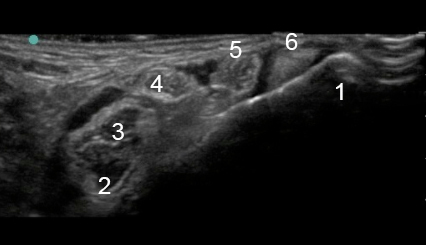

Foot & Ankle Medial Malleolus Image

1. Medial Malleolus

2. Flexor Hallucis Longus (FHL)

3. Nerve

4. Nerve

5. Flexor Digitorum Longus (FDL)

6. Posterior Tibialis Tendon